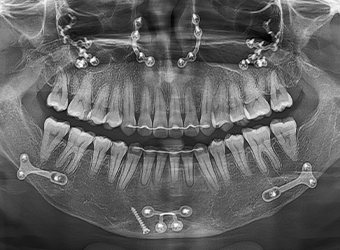

얼굴 턱뼈 수술에서는 절단 후 분리된 뼈를

새로운 위치에 고정하기 위해 고정핀을 사용합니다.

이 핀은 뼈가 충분히 회복된 후, 핀제거 수술을 통해 제거할 수 있습니다.

• X-ray, CT 등

방사선 촬영에서 핀이

보이고 싶지 않은 경우